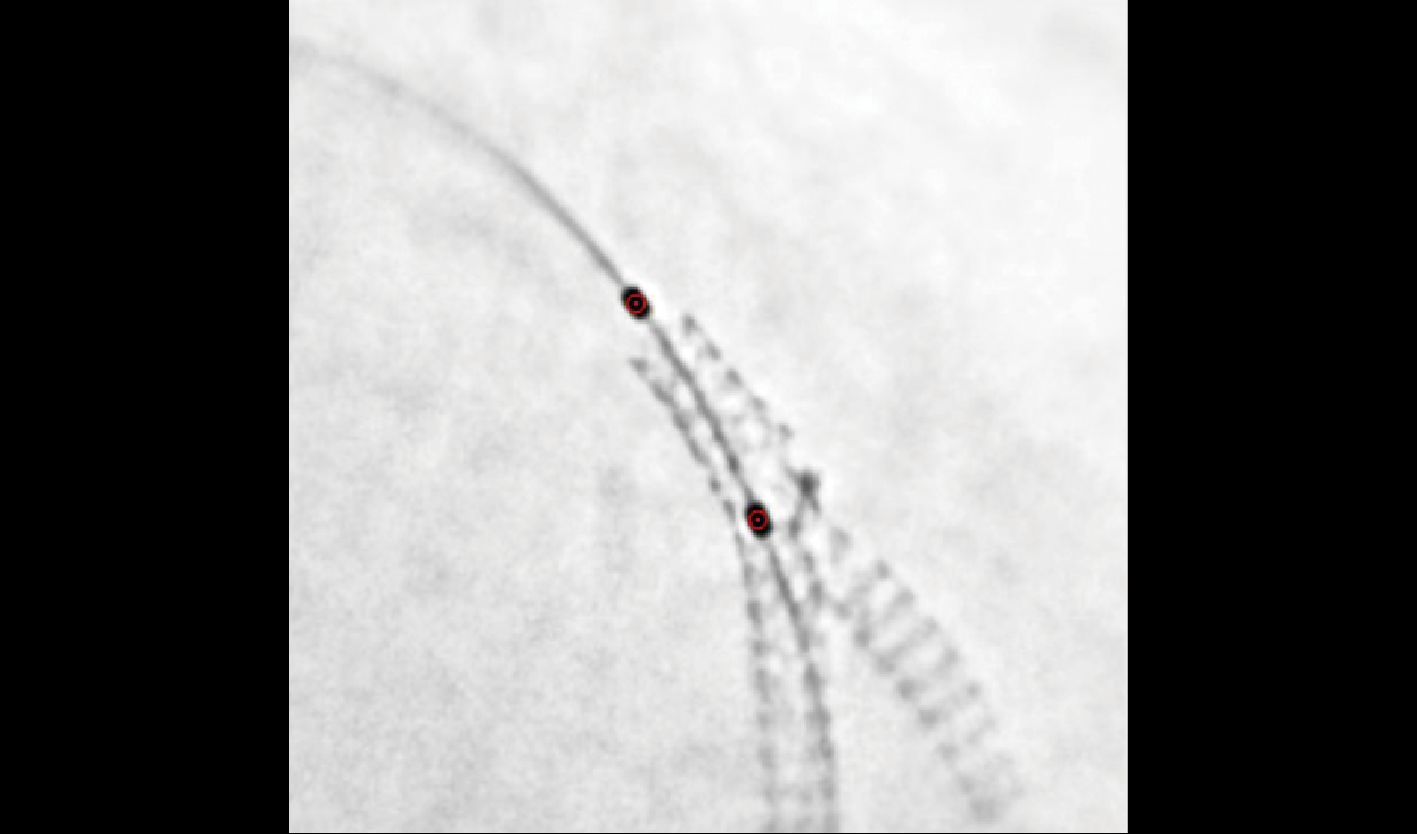

Quantum 3D/Quantum CT/Quantum Stent

2K超清影像链,精至微小血管一览无余

分辨率高